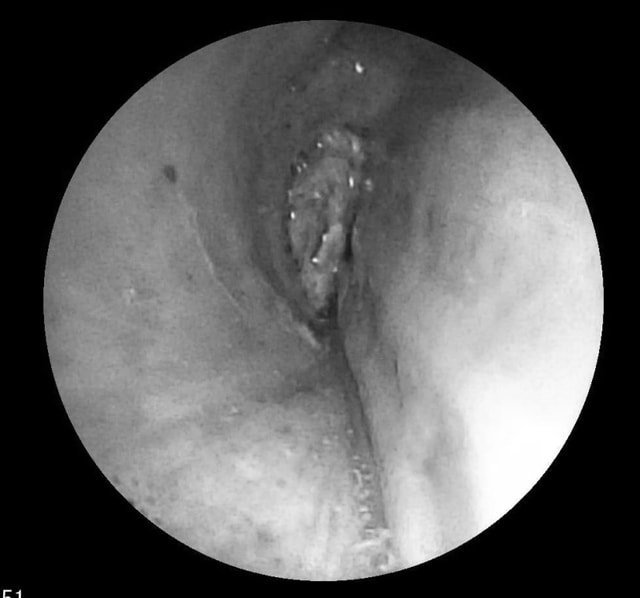

Ê-kíp của bác sĩ CKI Phạm Thị Út Trang – Phó Trưởng Khoa Nội hô hấp phối hợp với bác sĩ gây mê hồi sức đã nhanh chóng tiến hành nội soi phế quản ống mềm, phát hiện dị vật góc cạnh khoảng 1cm là hạt kha tử hình bầu dục, bề mặt trơn nhẵn, hai đầu nhọn nằm chắn, gây bít tắc trong lòng phế quản gốc phải, ngay sát vị trí chia nhánh phế quản phân thùy- khu vực giải phẫu hẹp, góc rẽ nhánh phức tạp khiến việc gắp dị vật gặp khó khăn. Ê-kíp nội soi can thiệp đã khéo léo tiếp cận và thành công gắp dị vật ra khỏi lòng phế quản.